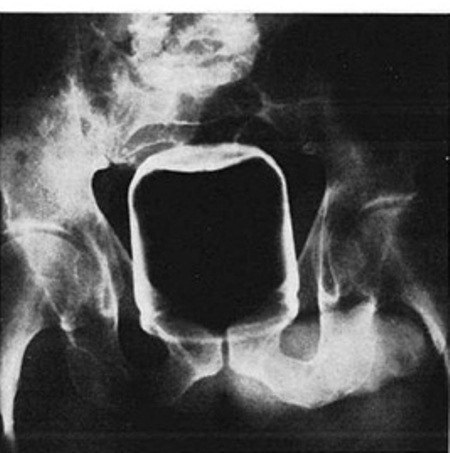

Μπουκάλι-σπρέι